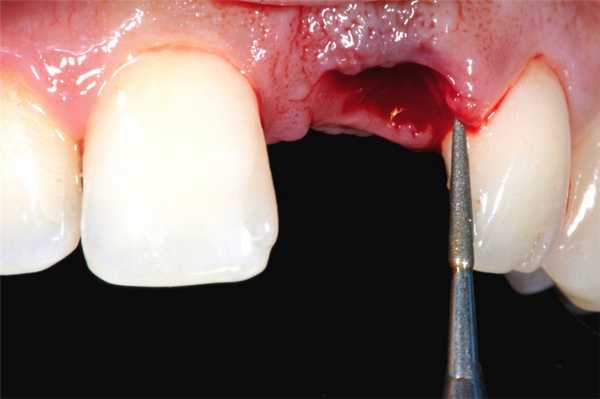

Перелом коронки или корня удаляемого зуба - самое частое из всех местных осложнений. В ряде случаев оно связано со значительным поражением зуба кариозным процессом, иногда зависит от анатомических особенностей строения корня и окружающей костной ткани (длинные, тонкие или сильно изогнутые корни при толстых межкорневых перегородках и неподатливых стенках лунки, неравномерное утолщение или значительное расхождение корней). Довольно часто это осложнение возникает вследствие нарушения техники операции: неправильного наложения щипцов, недостаточно глубокого их продвигания, резких движений во время вывихивания зуба, грубого и неправильного применения элеватора и т. д.

Повреждение десны и мягких тканей полости рта происходит в результате нарушения техники операции и грубой работы врача. Так, при неполном отделении круговой связки от шейки зуба соединенная с ним десна может разорваться во время выведения зуба из лунки. Чаще всего это случается при удалении зубов на нижней челюсти. Происходит разрыв слизистой оболочки с язычной стороны лентообразной формы.

Иногда щипцы накладывают и продвигают на корень или зуб не под контролем зрения, а вслепую (плохое открывание рта, недостаточное освещение операционного поля). Бывает так, что щечки щипцов захватывают десну, раздавливая ее во время смыкания щипцов и вывихивания зуба.

Разрыв слизистой оболочки может произойти, когда щечки щипцов продвигают глубоко под десну, пытаясь захватить верхнюю часть альвеолы. Если десна отделена от кости недостаточно хорошо, то она разрывается вдоль щечек. Предотвратить это осложнение удается путем рассечения десневых сосочков и круговой связки с наружной и внутренней стороны у двух соседних зубов и отделением слизистой оболочки десны на более значительном протяжении.